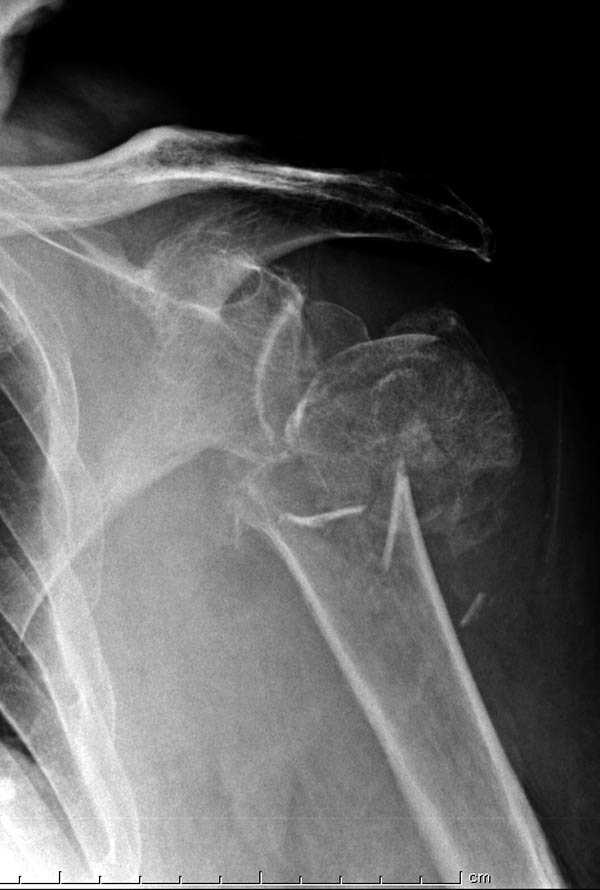

Пациентка Б.1953 г.р., врач-терапевт. Травма 27.11.08г. Падение с высоты роста. Выявлен закрытый не осложненный оскольчатый перелом хирургической шейки левого плеча со смещением. 02.12.08г. оперирована. Выполнена открытая репозиция и остеосинтез пластиной LCP Деост с дополнительной фиксацией отдельно лежащего фрагмента винтом. Послеоперационный период протекал без особенностей, заживление раны первичным натяжением. Швы сняты через 10 дней. Иммобилизация левой верхней конечности клиновидной подушкой 4 недели. По окончании срока – рентген-контроль и умеренная разработка плечевого сустава. В течении месяца функция левого плечевого сустава восстановилась удовлетворительно: поднятие руки до 110 гр., отведение - 90 гр. и до 110 гр. отведение с лопаткой. Отведение руки назад – 20 гр. Наружная и внутренняя ротация – 20 гр. Пациентка по настоянию самостоятельно вышла на работу. 27.03.09 при контрольном осмотре жалоб не предъявляет, болевой синдром в левом плечевом суставе отсутствует. Отведение плеча активно до 90 гр, пассивно с лопаткой до 110 гр., поднятие – 110 гр, отведение назад 20 гр, наружная и внутренняя ротация по 20 гр. На контрольных рентгенограммах отмечается смещение металлоконструкции, ротация головки плеча с приведением дистального отломка на 13 гр. и смещением к зади на 30 гр. Рентгенограммы прилагаются. Ваш взгляд на дальнейшую тактику лечения пациентки?

Нет аксиальной проекции сразу после вмешательства. Возможно, никакого значительного смещения нет, все осталось так, как первично сопоставили...и,

Уважаемый Евгений, похоже, что первый и второй Р-снимки выполнены несколько в разных положениях(ротация) плечевой кости, в связи с этим создается впечатление смещения пластины. Остеосинтез выполнен при угловом смещении отломков.Таковым и остался. Данная ситуация была бы очевидна гораздо раньше, если бы при контрольной Р-графии были выполнены снимки в 2-х проекциях.(Не в обиду, сам иногда выполняю только один).

Здесь пример открытой репозиции 57 летнего с переломом плеча (1,2) смещение обнаружено на интероперационном снимке. При нормальной прямой проекция (3) угловое смещение обнаружили в аксиальной проекции (4)

После устранения смещения пластина установлена выше (5,6,7) и финальные снимки (8,9,10)